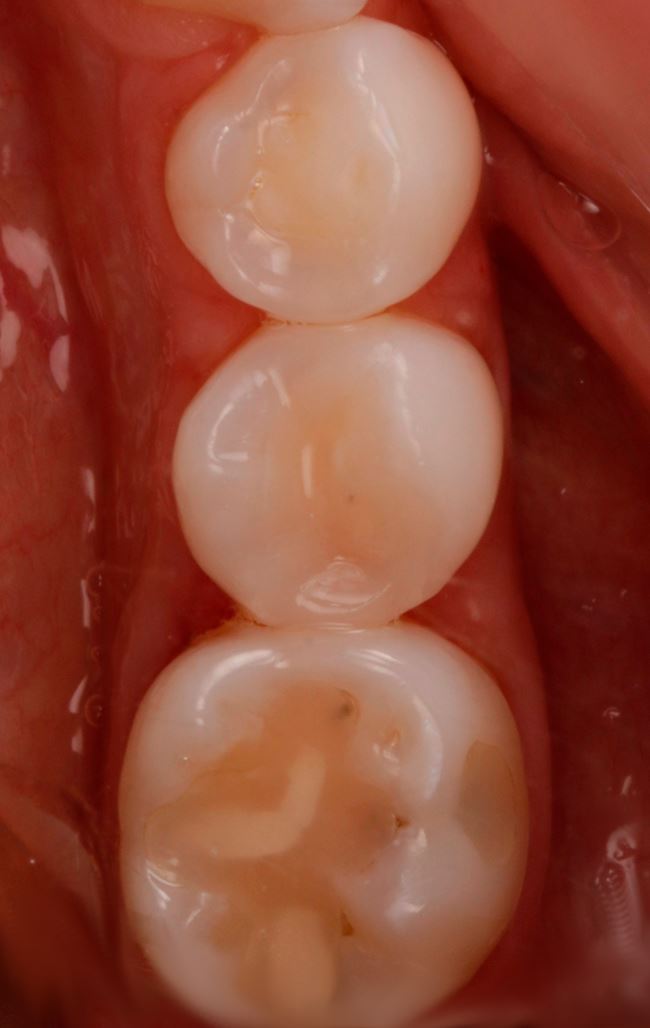

W przypadku zęba 45 wyraźnie widać, że DIAGNOcam się sprawdził, gorzej ze zdjęciem skrzydłowo-zgryzowym. Teraz pozostało już tylko założenie formówki (ryc. 11), wypełnienie ubytku, w tym przypadku nanohybrydowym materiałem kompozytowym Harmonize (Kerr) (ryc. 12 i 13), dostosowanie wypełnienia i wypolerowanie (ryc. 14). Chociaż to jeszcze nie wszystko. Ostatnią czynnością powinno być zmotywowanie pacjentki do codziennego stosowania nici dentystycznej. Obrazy z DIAGNOcamu świetnie się do tego nadają.

Ryc. 12. Ząb 45 po założeniu formówki jednościennej i klina.

Ryc. 13. Odtworzenie ściany stycznej w zębie 45 nanohybrydowym materiałem kompozytowym Harmonize Enamel A3.

Ryc. 14. Ubytek w zębie 45 bezpośrednio po wypełnieniu materiałem Harmonize Enamel A3.

Ryc. 15. Ząb 45 po leczeniu.